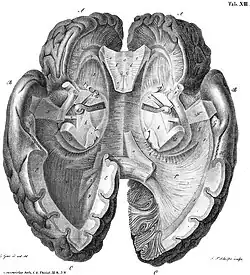

Нейроанатомия. Эпонимы

В последние годы жизни в Галле Рейль заинтересовался нейроанатомией, особенно после лекции, которую летом 1805 прочитал френолог Ф. И. Галль. Иоганн Христиан Рейль начал изучать мозжечок, публикуя большинство работ в 1807-1809. Он известен в анатомии мозга множественными эпонимами после изучения его строения и химического состава:

- Дугообразный пучок (пучок Рейля, лат. fasciculus arcuatus) соединяет клетки язычка, клетки ядра шатра с латеральным, медиальным и верхним преддверными ядрами;

- Рейля циркулярная борозда (синоним: круговая борозда островка, лат. sulcus circularis insulae);[15]

- Рейля углубление (синоним: долинка мозжечка, лат. vallecula cerebelli);

- Рейля треугольник (синоним: треугольник петли, лат. trigonum lemnisci);

- Рейля связка (синоним: медиальная петля, лат. lemniscus medialis);

- Рейля петля (синоним: петля мозговой ножки, лат. ansa peduncularis);

- Рейля островок (синоним: островковая доля, лат. lobus insularis);

- Рейля волокна (синоним: латеральные полоски мозолистого тела, лат. striae longitudinales laterales);

- Он первым описал структуру, известную как покрышка (лат. tapetum) мозолистого тела;

Рейля островок (здесь и далее структура отмечена красным)

Рейля островок (здесь и далее структура отмечена красным) Рейля петля

Рейля петля Треугольник Рейля

Треугольник Рейля Углубление Рейля

Углубление Рейля

Ещё в «Рапсодии (восторженной речи) об использовании психологической терапии для душевно больных» Рейль писал:

«Мозг — постигается как комплексное производное искусства, состоящее из большого количества взаимосвязанных тел, что находятся в целенаправленной связи друг с другом».

Изменение одного из них ведет к изменению мозга в целом. А так как мозг — орган души, её воля тогда также нарушается. Так работает мозг сумасшедшего. Мозг и рассудок неразрывно связаны. Связан он и с остальной, ниже уровнем, нервной системой. Поражается мозг — поражается рассудок.

Из других эпонимов хорошо известен палец Рейля (лат. Digitus mortuus)[16], линии Бо[17]-Рейля на ногтях (описаны Рейлем за 50 лет до Д. О. С. Бо, в 1796)[18] и канатик Рейля.

Рейля канатик

Рейля канатик